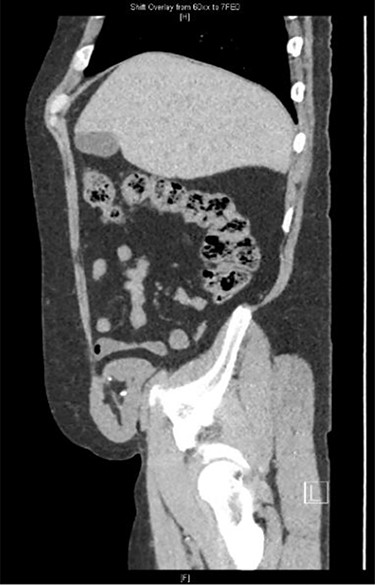

His workup was included but not limited to basic labs (CBC, CMP and UA), a renal transplant ultrasound, and a CT of the abdomen and pelvis. The CT scan revealed herniation of the right-sided donor kidney through an incisional hernia (Figs 1 and 2).

Sagittal view CT: herniation of the transplanted kidney through the right abdominal wall.